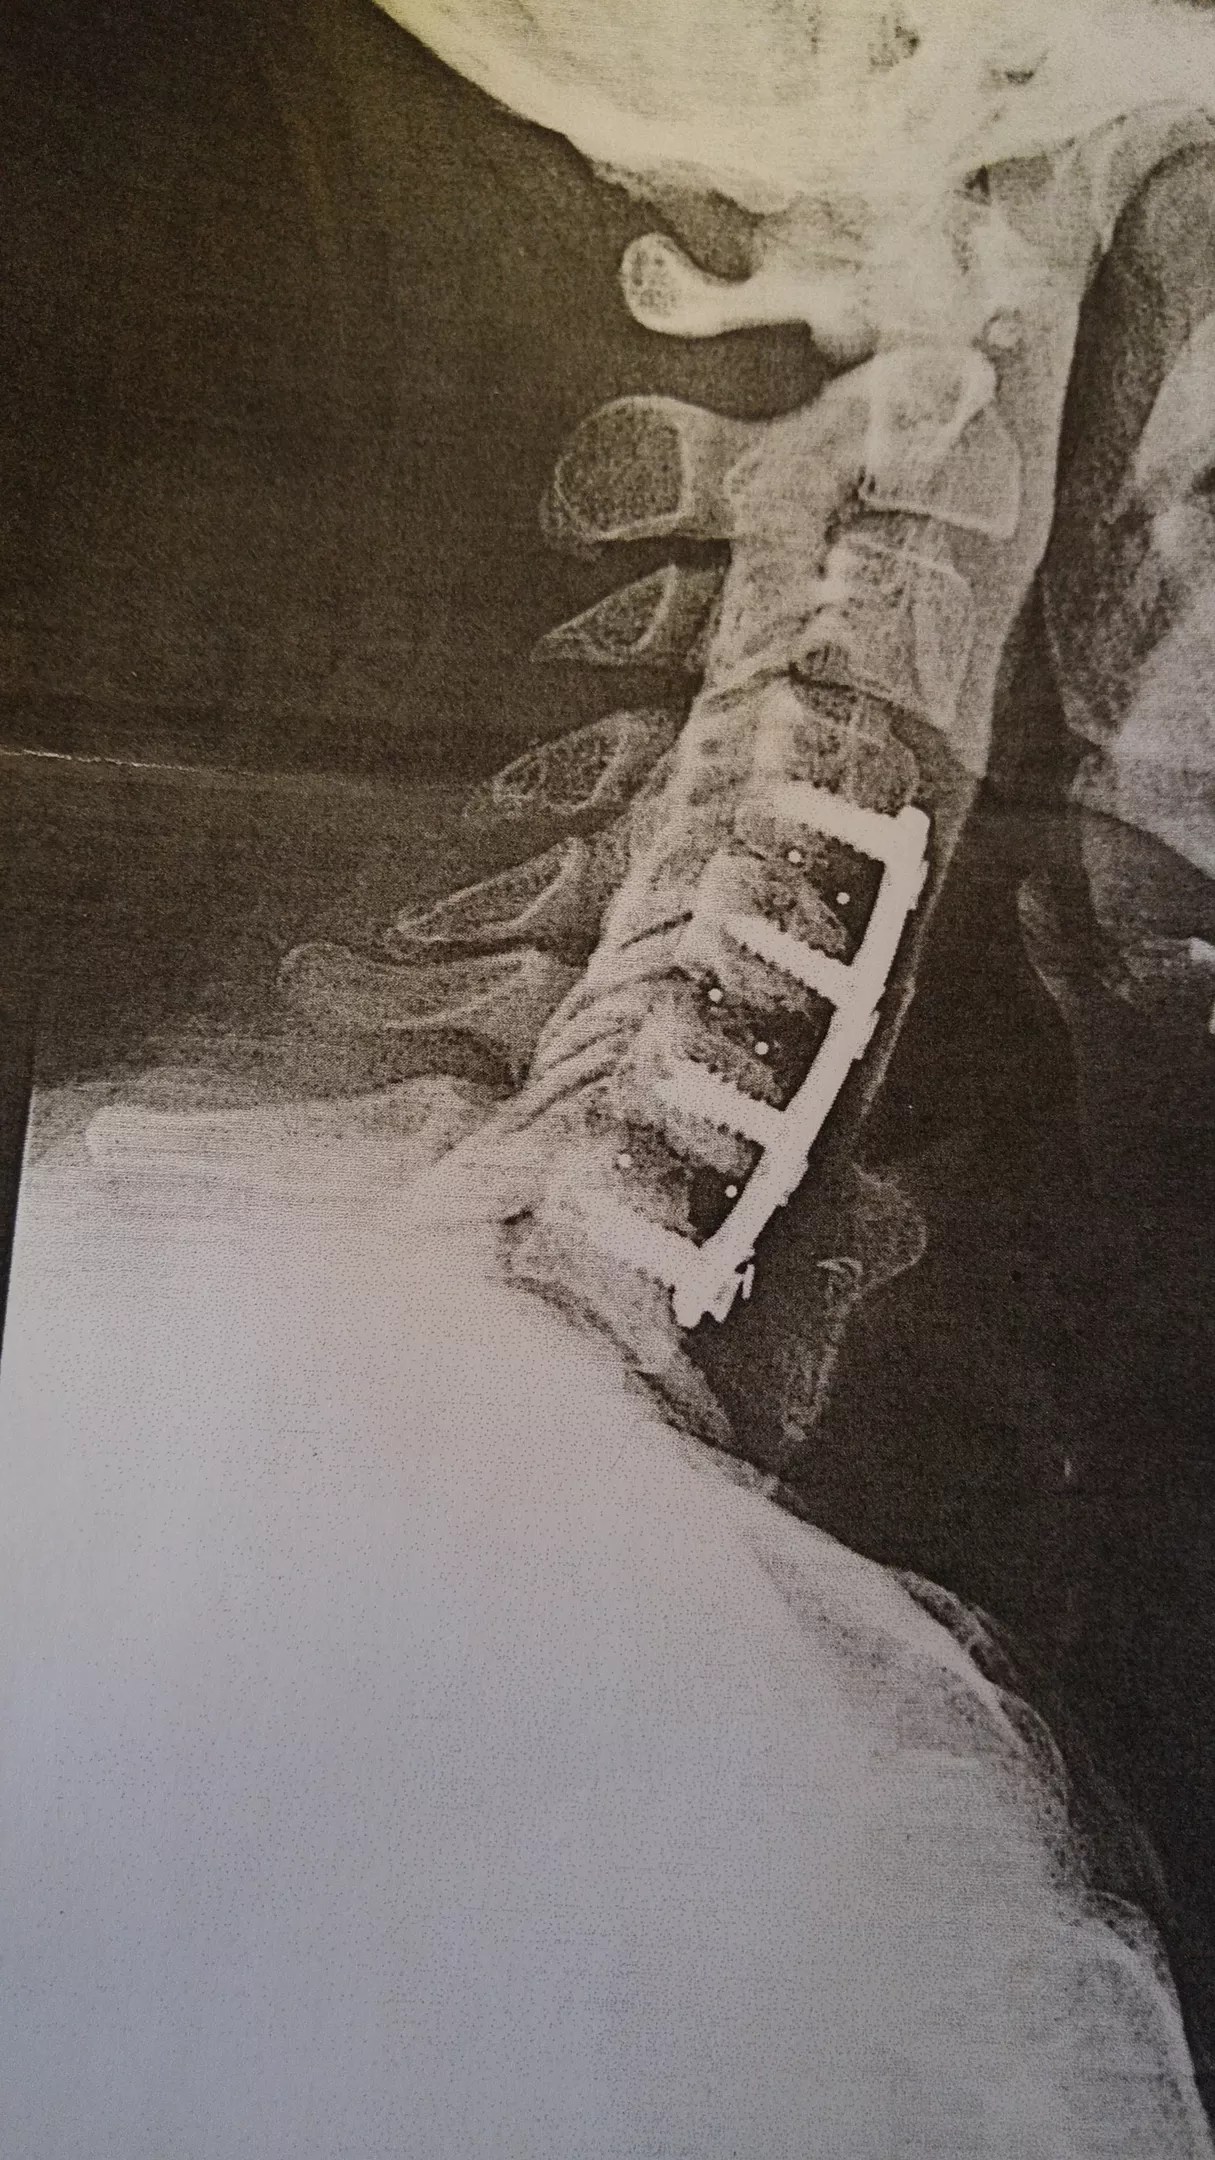

Garrett’s X-ray after his first surgery, which he says the surgeon botched.

Courtesy Scott Garrett

After multiple spinal surgeries, one of which was botched, the Dallas native was left with steel rods and screws keeping his neck in place and chronic pain that he compares to someone taking a baseball bat and beating him on the back of the neck. He feels it in his sleep.

The simple procedure consisted of taking some cadaver bone, sticking it between four of his vertebrae and fusing it all together using steel rods and screws. Garrett says the surgeon used the wrong kind of bone and didn’t tighten the screws, causing one of them to work its way out and nearly impale his trachea.